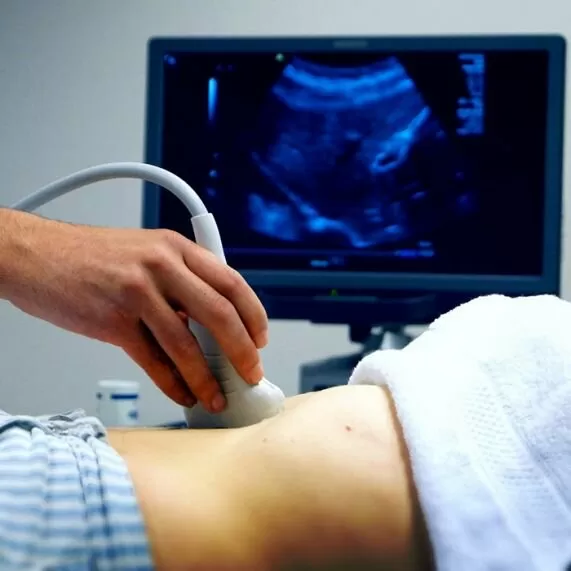

It is performed in two ways: transabdominally and transvaginally.

For transabdominal examination (through the abdominal wall) it is necessary to fill the bladder. Why drink at least 1 liter of non-carbonated fluid 2 hours before the examination or do not urinate for 3-4 hours.